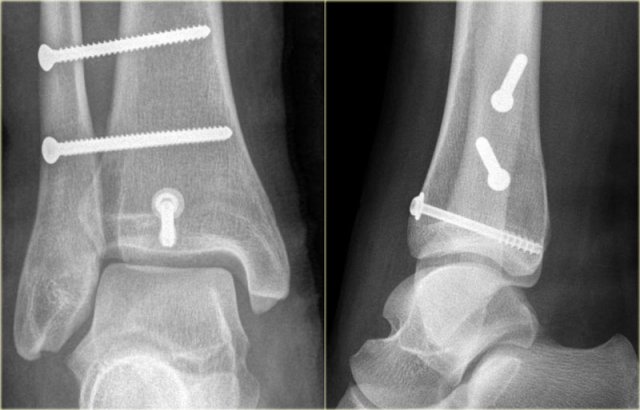

Here we have images of an extremely difficult case.

This woman had a distortion of the ankle and had pain on both medial and lateral side.

She was referred to the radiology department by her general practitioner.

The technician made the standard AP-, Mortise- and lateral view and showed them to the radiologist, who was a little bit puzzled.

First study the images and then continue reading.

The findings are:

• Soft tissue swelling both medial and lateral (red arrows).

Especially the medial swelling should make you consider a pronation exorotation injury (Weber C).

• Lucent line on Mortise view (black arrow) and lateral view. This should make you consider a tertius fracture.

The radiologist decided first to order a CT to find out if there really was a tertius fracture.

Continue with the CT and be amazed.

Scroll through the images.

It is amazing, that such a large tertius fragment is so difficult to see on the radiographs.

Also notice the soft tissue swelling on the medial side indicating rupture of the medial collateral ligaments (arrow).

Do you have an idea what kind of injury this is?

Medial soft tissue swelling and a tertius fracture are both indications of a Weber C or Pronation Exorotation injury.

Since there is no fibula fracture seen on the x-rays of the ankle, there must be a high fibular fracture.

At physical exam there was some swelling on the medial side and although the patient did not complain of any pain higher in the lower leg, there was some tenderness when the fibula was palpated.

This spot was marked and a fracture was found.

This case illustrates the importance of medial soft tissue swelling aswell as the finding of a tertius fracture.

According to Lauge Hansen we can conclude that this patient first had a rupture of the medial collateral ligaments (stage 1), followed by a rupture of the anterior syndesmosis (stage 2) and a high fibula fracture (stage 3) and finally an avulsion of the posterior malleolus, i.e. PE stage 4.

At surgery the ankle was found to be unstable and syndesmosis screws were inserted.

There was an indication for fixing the posterior malleolar fracture, since the fragment involved more than 25% of the articular surface of the distal tibia.